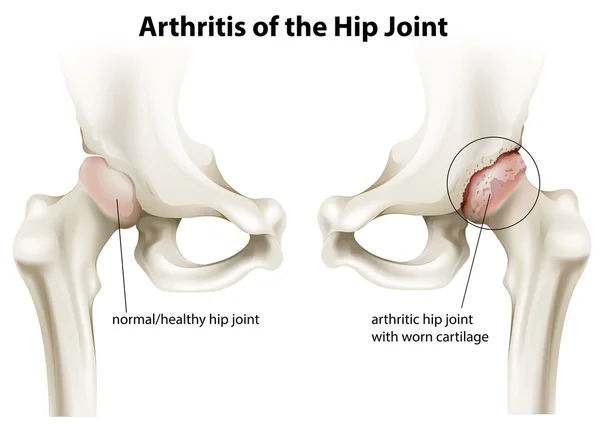

Остеоартроз является хроническим заболеванием суставов, в основе которого лежит дистрофическое изменение хрящевых тканей с их последующим разрушением и возникновением характерных деформаций. Хрящ истончается, становится шероховатым, растрескивается, теряет прочность и эластичность. В результате этого патологического процесса формируются краевые костные разрастания — остеофиты.

Болезнь чаще поражает крупные суставы. К специалистам обращаются пациенты, у которых диагностируется остеоартроз коленного сустава, который нередко формируется в результате бытовых и профессиональных травм. У пожилых людей на фоне остеопороза, нарушений обмена веществ и генетической предрасположенности может развиваться остеоартроз тазобедренного сустава, приводящий к инвалидизации и значительным двигательным ограничениям в будущем. Люди пенсионного возраста в группе риска по развитию опорно-двигательных нарушений. После 60 лет у большинства из них развивается остеопороз и остеоартроз кистей рук и других крупных суставов.

На рентгенограммах тазобедренный сустав сохраняет нормальную форму, суставная щель умеренно или неравномерно сужена с субхондральным склерозированием костных суставных поверхностей, непостоянными краевыми костными разрастаниями (I стадия).

Рентгенологически суставная щель может быть равномерно или неравномерно сужена, ацетабулярная суставная впадина уплощена, присутствуют явления субхондрального склероза, краевые костные разрастания. Конфигурация головки бедренной кости, как правило, не нарушена (II стадия).